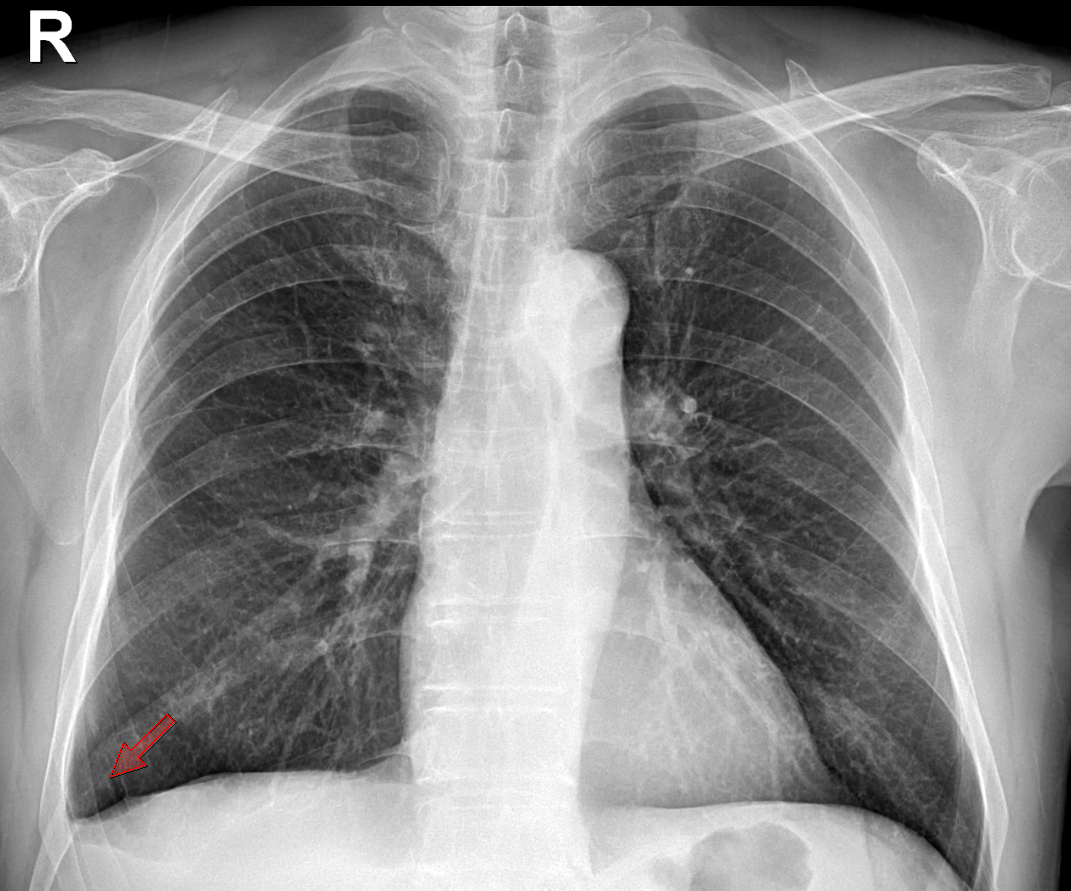

흉막 비후는 흉막이 두꺼워진 것을 말합니다. 보통 흉부 엑스레이나 CT 촬영으로 많이 확인하는 상탭입니다. 흉막은 폐를 둘러싸고 있는 얇은 막으로, 폐가 부드럽게 움직일 수 있게 도와주는 역할을 합니다.

그런데 여러 이유로 흉막이 두꺼워지는 경우가 있습니다. 이를 흉막 비후라고 부르며, 이는 폐나 흉막에 무언가 자극이 있거나 염증이 생기면서 발생할 수 있습니다.

흉막 비후는 흉막의 여러 부위에서 발생할 수 있으며, 발생 위치에 따라 그 원인과 임상적 의미가 달라집니다. 흉막 비후가 잘 생기는 부위는 주로 폐 첨부, 늑횡격막(횡격막 부근), 심횡격막, 그리고 벽측 흉막으로 나눌 수 있습니다.

횡격막에 인접한 부분에서도 비후가 잘 생길 수 있습니다. 이 부위의 비후는 주로 다음과 같은 원인과 관련이 있습니다.

● 흉수: 가슴에 물이 차는 흉수 상태로 인해 횡격막 부근의 흉막이 자극을 받아 두꺼워질 수 있습니다.

● 간경변과 심부전: 간경변이나 심부전으로 인해 흉수가 고이면서 흉막이 두꺼워지는 경우가 많습니다.

● 석면 노출: 석면에 오래 노출된 경우에도 늑횡격막 부위에 비후가 생기며, 시간이 지나면 중피종이라는 암으로 발전할 가능성이 있습니다.